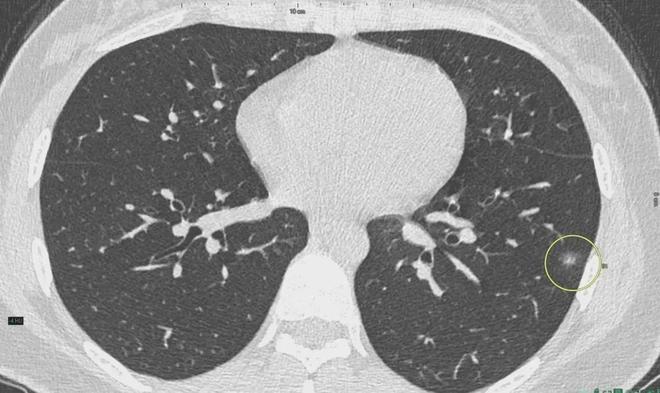

6、定期體檢:定期進(jìn)行肺部檢查,及時發(fā)現(xiàn)并治療肺結(jié)節(jié)。

對于已經(jīng)發(fā)現(xiàn)肺結(jié)節(jié)的患者,應(yīng)及時就醫(yī),進(jìn)行進(jìn)一步的檢查和治療,醫(yī)生會根據(jù)患者的具體情況制定個性化的治療方案,包括藥物治療、手術(shù)治療等,早期發(fā)現(xiàn)、早期治療是提高肺結(jié)節(jié)治愈率的關(guān)鍵。